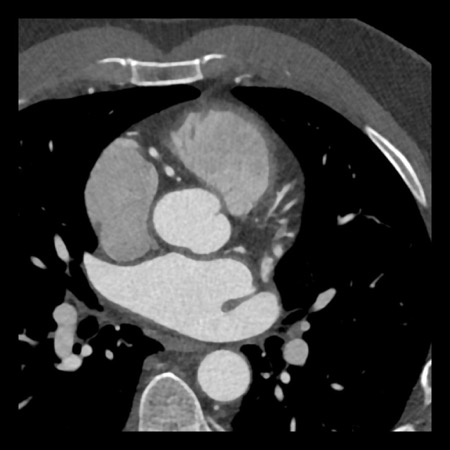

case 1 – CAD-RADS 2/P1

First, scroll through the scan.

Not all images are included. Some images without any abnormalities are skipped

from the series.

How would you describe the findings on the coronary CTA?

The findings are:

- Agatston score of

this patient was 14 (P1). Please, also note the calcification of the aortic valve. - Some partially

calcified and calcified plaques are present in the LAD with mild stenosis

(25-49%). - Calcified-plaque in

the LCX causing minimal stenosis (<25%). - Non-calcified

plaque in the distal RCA causing minimal stenosis (<25%). - This patient classifies

as CAD-RADS 2/P1, which means no further workup is needed.